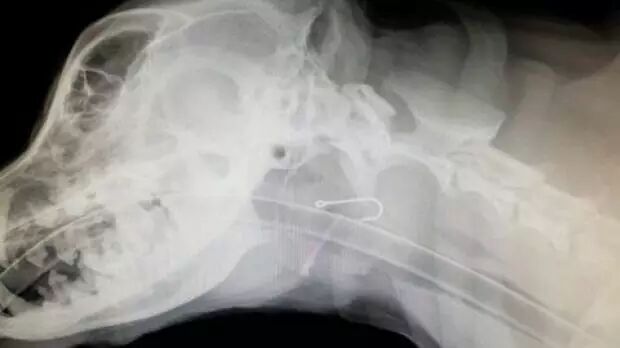

近日,一位珀斯渔民在钓鱼时随手将鱼钩扔在了地上,而随后,他的宠物狗将这个鱼钩吞了下去,连带被吃下去的还有一段大约四英寸长的钓鱼线。事情发生后,这位渔民也发出了自己的提醒,带宠物狗出去钓鱼时一定要妥善处理好自己的鱼钩。

Mike Diamond带着他的狗来到了Kingsley Veterinary Hospital进行了观察,两个小时后,X光检测结果出来了。“医生发现我的狗吃下去了一个鱼钩,大小大约和小拇指的第一节差不多大,但是鱼钩上还连着一条四英寸长的钓鱼线。不过医生们没有对它做手术,只是用了一对长钳子就把东西给取出来了,据说鱼钩卡在了它舌根的后面。”

在经过为期一周的抗生素治疗,且吃了两个星期的软食物之后,Mike Diamond狗终于完全康复了。这次治疗的费用总共花了一千多澳元,但是Mike Diamond担心其他的动物也会遭受同样的不幸,于是他提醒其他钓鱼者要谨慎处理鱼钩,不要被其他动物误食。“渔民们有时候很专业,但有时候却也很外行,如果他们把鱼钩随便丢弃的话,不仅仅是狗,猫,鸟,甚至是小孩,都有可能会因此受伤,所以这对每个人来说都是危险的行为。”